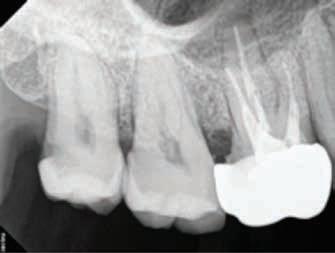

Periapical Tooth #3 (Root Canal Treatment)

Periapical Tooth #14 (Root Canal Treatment)

#3 #14